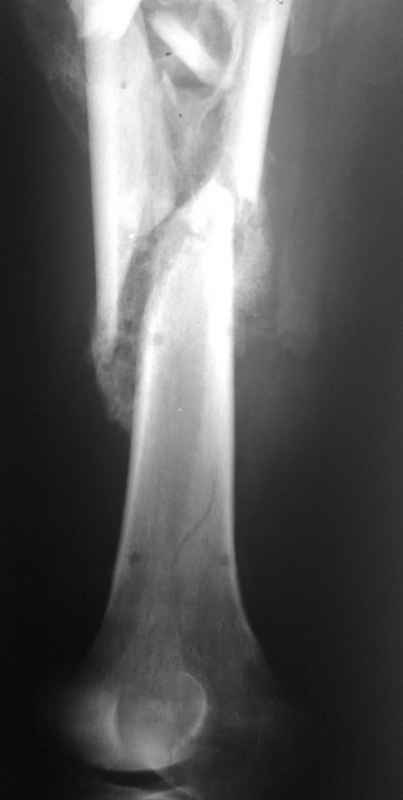

Re: Неправильно срастающийся оскольчатый перелом бедра